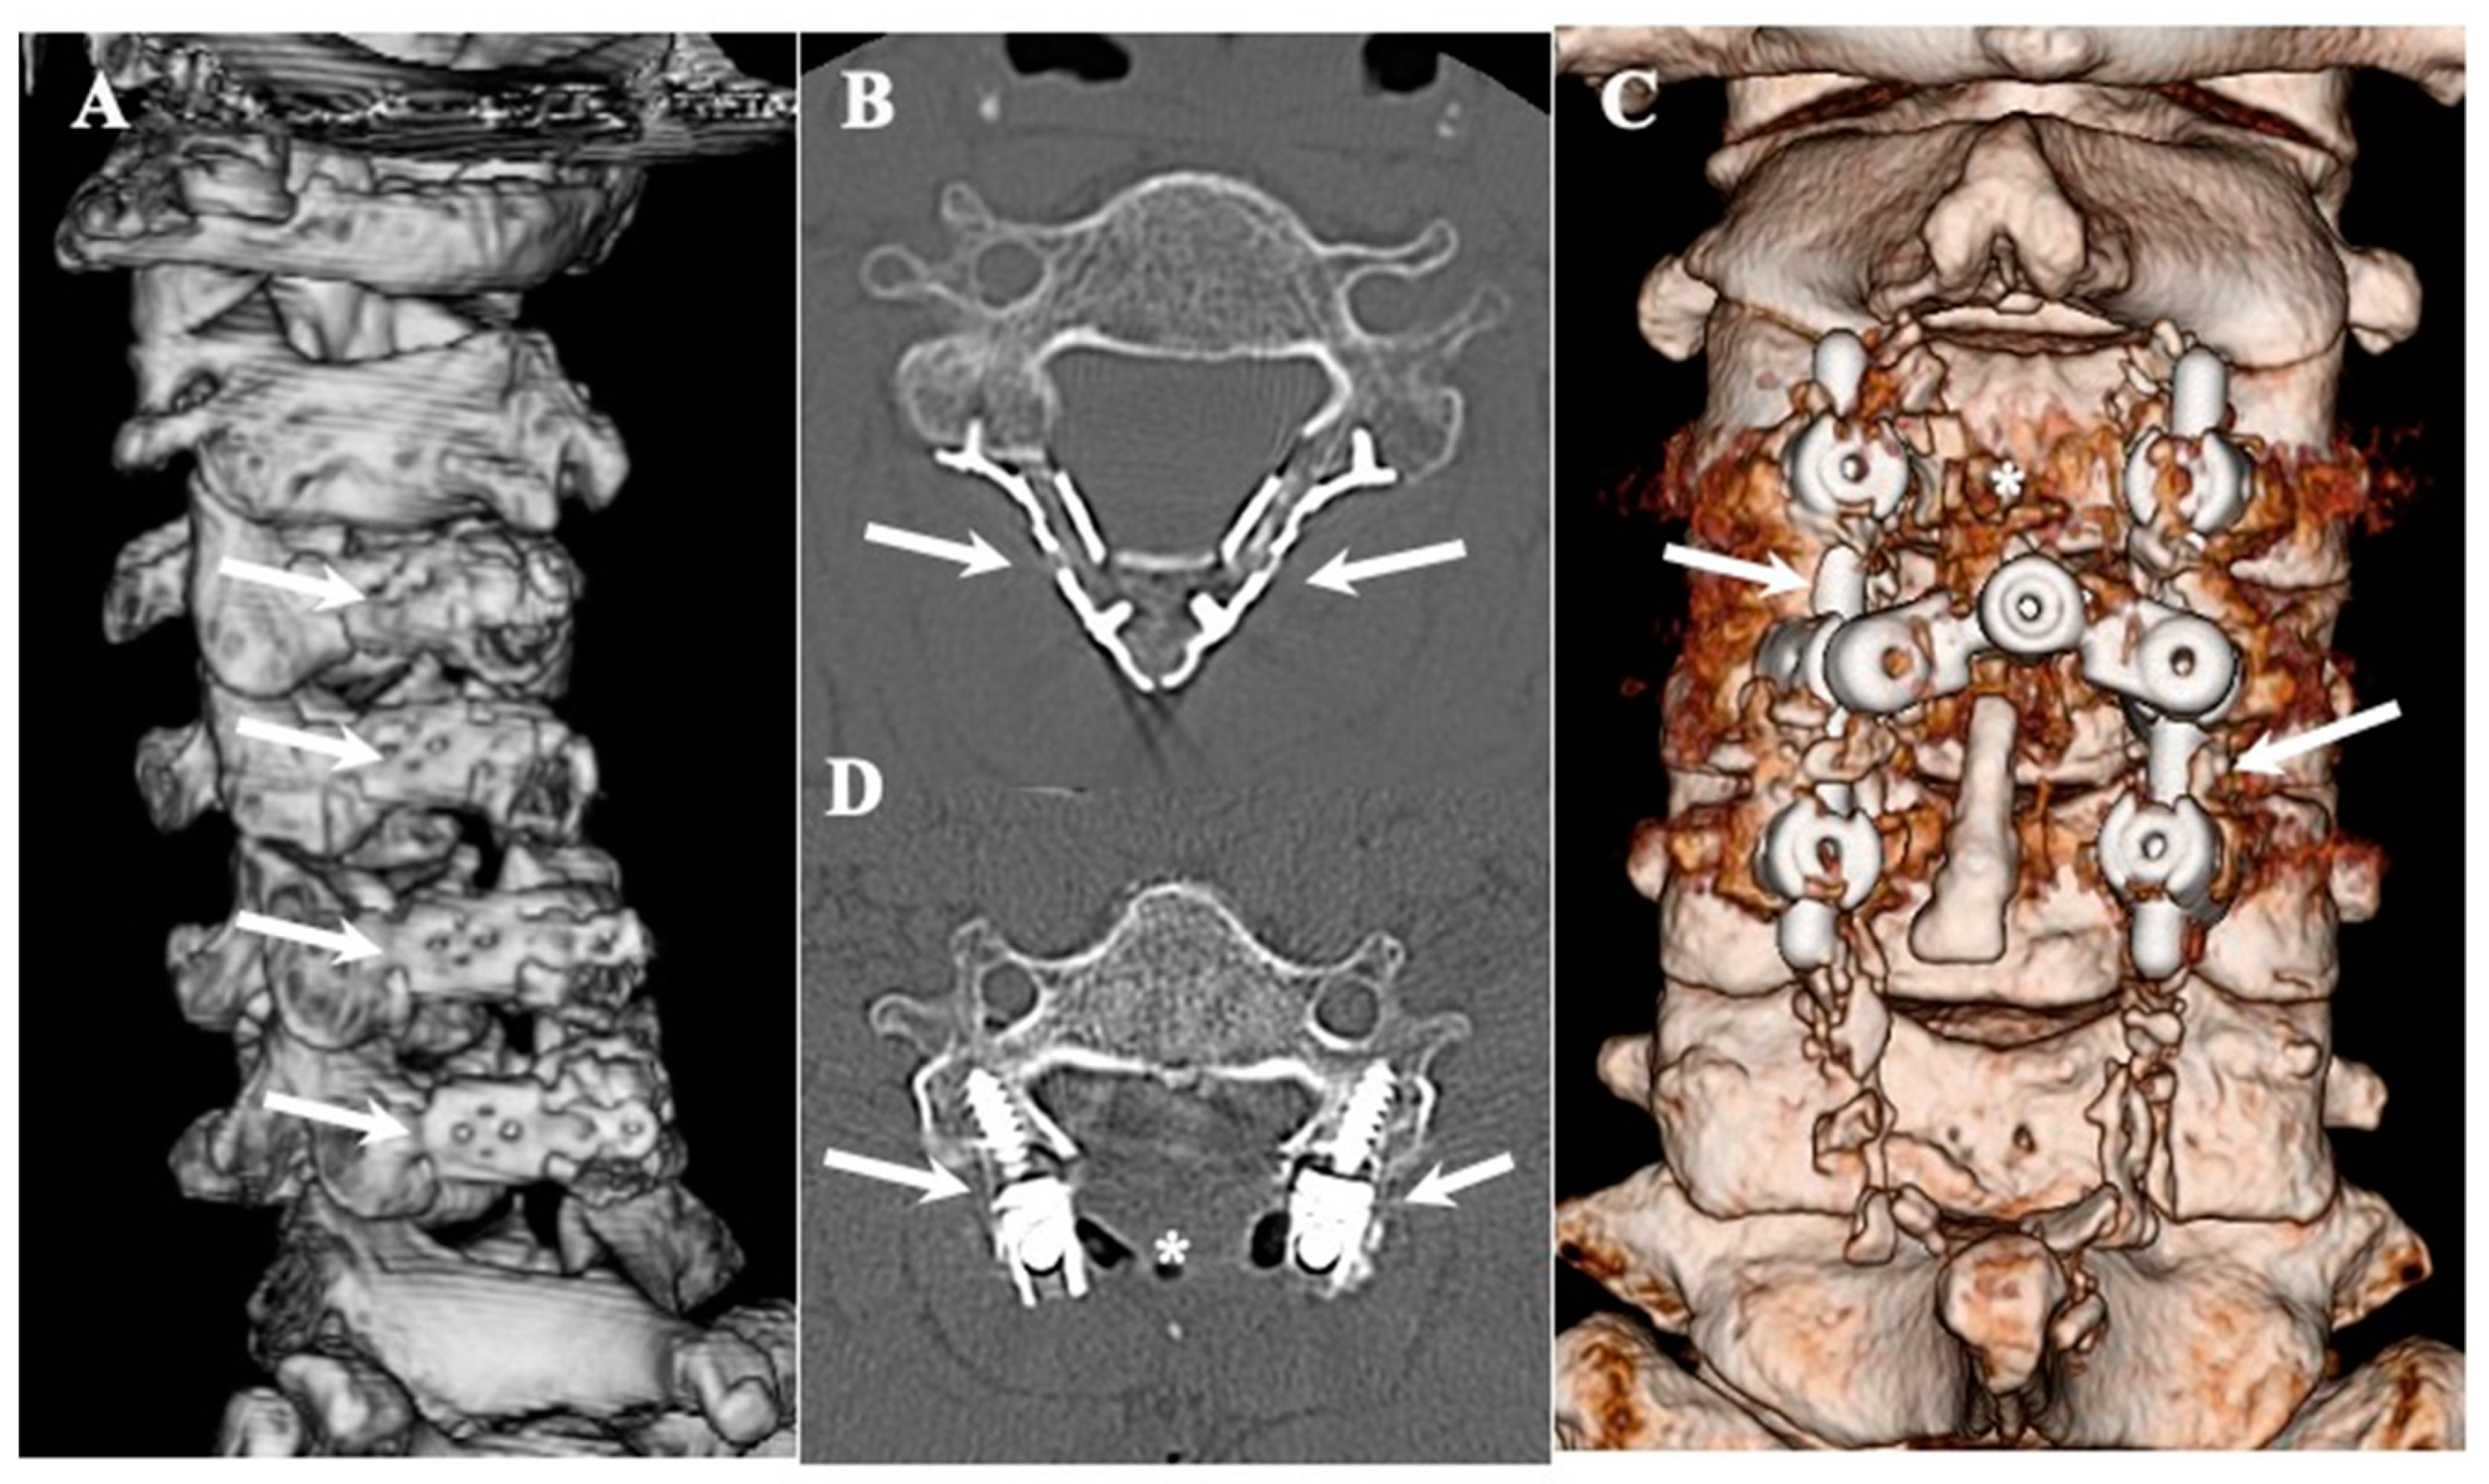

2.2.2. Surgical Indication and Procedure (Figure 1 and Figure 2, Table 4)

CLF: Conventional laminectomy or en-bloc laminectomy and laminoplasty using basket-type titanium plates were performed after the dissection of the CLF (Figure 1A,B) [46,47,48]. For cases with instability, single-stage posterior decompression (laminectomy) and posterior lateral fixation (laminectomy with posterior lateral fixation [PLF]) using instrumentation were performed (Figure 1C,D) [49]. In most of the cases of CLF, there was no adhesion between the ligamentum flavum and the dura mater, and calcification did not extend to the intervertebral foramen. Therefore, en-block laminoplasty was generally considered the primary choice. For instances where calcification was extensive, such as when calcification extended to the intervertebral foramen, laminectomy and posterior lateral fixation were performed.

Figure 1.

Three-dimensional and two-dimensional CT images of CLF. Three-dimensionally reconstructed CT image showing changes after en-bloc expansive laminectomy and laminoplasty using basket-type titanium plates (arrows) (A) and axial image (B). Three-dimensionally reconstructed CT image showing changes after single-staged posterior decompression (asterisks) and posterior lateral fixation using lateral mass screws and rods (arrows) (C) and axial image (D).

CLF: Laminectomy was performed in two cases, laminoplasty was performed in eight cases, and single-stage laminectomy with PLF was performed in five cases with instability (Figure 1 and Figure 2) [46,47,48,49]. Of the eight cases that underwent expansive laminoplasty, five underwent en-block expansive laminoplasty using basket-type titanium miniplates with HA and collagen sponge (Figure 1) [48].

OLF: Laminectomy was performed in 12 cases, expansive laminoplasty was performed in 5 cases, and single-stage laminectomy with PLF was performed in 3 cases with instability [46,47,48,49]. Of the five cases that underwent expansive laminoplasty, three underwent en-block expansive laminoplasty using basket-type titanium miniplates with HA and collagen sponge (Figure 1) [49]. In terms of the intraoperative findings, OLF was in contact with the dura matter in 10 cases and adhered to the dura matter in 5 cases. The dura matter was opened by OLF resection and sutured using a 6–0 Nylone thread. The DuraGen® was covered with fibrin glue.

4.3. Surgical Treatments and Outcomes in CLF and OLF (Figure 1 and Figure 2; Table 4)

CLF: In most CLF cases, to prevent post-operative kyphosis in cases where calcification did not extend to the intervertebral foramen nor adhered to the dura mater, we attempted en-block laminoplasty. The ligamentum flavum, including CLF, can be removed without damage through en-block laminoplasty because the calcification is present inside the ligament and does not reach the surface of the ligament or cause adherence to the dura mater. However, caution is required when excising the ossified portion of the ligamentum flavum from the dura mater, as illustrated in Figure 2. In some instances, we deliberately left the calcification thin and chose not to detach it from the dura mater.

OLF: In OLF, as an operative procedure, laminectomy was generally indicated. But we think that to prevent post-operative kyphosis, we should try to perform laminoplasty for the possible case where ossification does not extend to the intervertebral foramen nor adhere to the dura mater, as illustrated in Figure 5B,B’. Since most cases of OLF exhibit adhesion to and penetration into the dura mater, caution is required during OLF removal, as illustrated in Figure 2. In cases with adhesion to the dura mater, it may be necessary to carefully preserve the OLF or suture defects in the dura mater after the dissection of the OLF (Figure 2) [49,51].